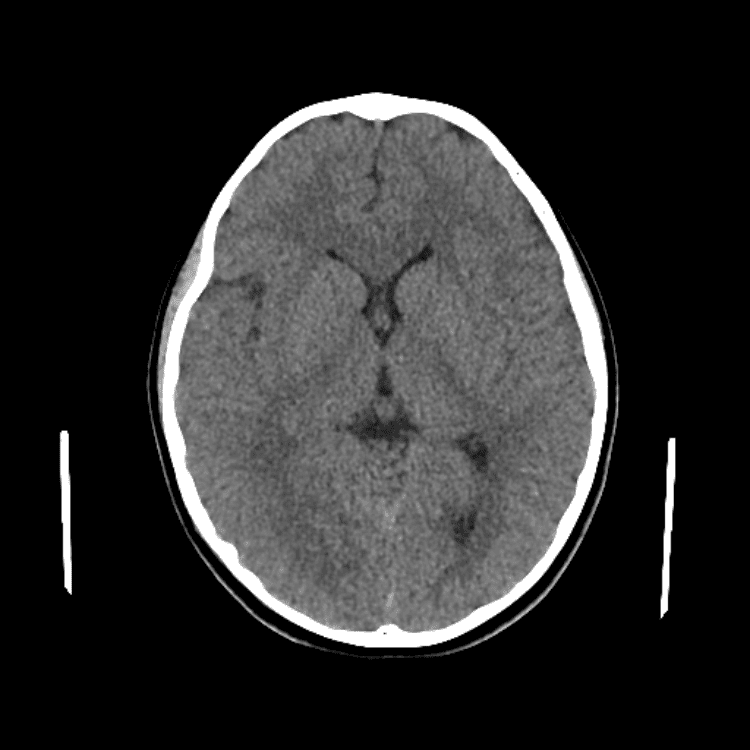

Nontraumatic Brain

Practice